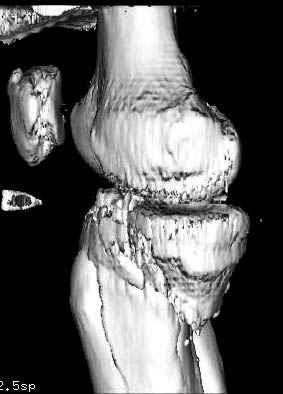

Интрамедуллярный остеосинтез диафизарного перелома тут возможен, но в первую очередь надо с помощью КТ уточнить повреждение суставного конца. Импрессионный перелом наружного мыщелка явный есть, может, и медиальная колонна повреждена, так что надо в первую очередь планировать открытую репозицию с замещением дефекта с фиксацией пластиной или аппаратом. Если получается технически, можно поверх уже синтезированного стержнем диафиза.

Уважаемый Александр Николаевич! Прошу прощения за некачественные сканы. КТ вообще-то реально, но сложности с транспортировкой больного в соседний корпус (такая перевозка и перекладывание для больных - дополнительная травма). По Р-граммам медиальный отдел вроде целый, но наружный мыщелок "отклячен" и суставная поверхность явно просела. У нас весь вопрос в методе фиксации или же их сочетании - одна пластина, опорная пластина и стержень (я так понял, что вы предлагаете сначала фиксировать диафиз, а потом заняться мыщелком?), винты и стержень, аппарат...Опять же состояние м/тканей (плотный отек, кровоизлияние)...

Пациенту сделали КТ - ухитрились сделать на шине Белера (не давал положить прямую ногу) - срезали передний отдел. Планируется на пятницу (24.12) на операцию - синтез длинной мыщелковой LCP-пластиной Synthes :). Отек ближе к слову умеренный (окружность голени +4 см по сравнению со здоровой). КТ и снимок на вытяжении прилагаются.

На представленных предоперационных срезах КТ огромный задне-медиальный фрагмент расположен больше кзади, чем медиально. Для планирования, кроме поперечных срезов, надо ориентироваться на корональные срезы, которые укажут топографию верхушки медиального фрагмента.